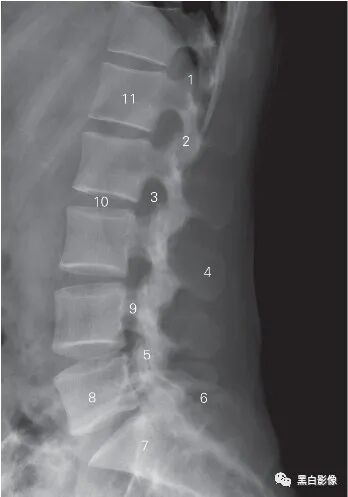

图6-5 腰椎侧位DR 平片

1 上关节突 superior articular process 2 下关节突 inferior articular process

3 椎间孔 foramen intervertebrale 4 棘突 spinous process

5 关节突关节 zygapophyseal joint 6 髂骨 ilium

7 骶骨 sacrum 8 第5腰椎 5th lumbar vertebra

9 椎弓峡部 isthmus vertebral arch

10 L2/3椎间隙 L2/3 lumber intervertebrale space

11 第1腰椎椎体 1st lumbar vertebral body

![]()